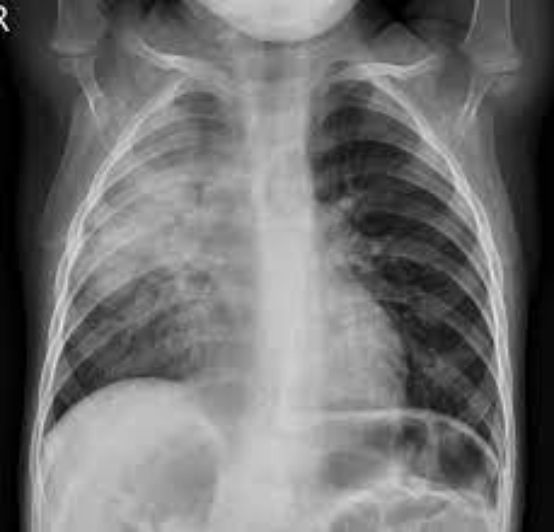

Pediatric Imaging

Child-friendly imaging including X-rays, ultrasound, and CT scans. Specialized techniques to minimize radiation exposure in children.